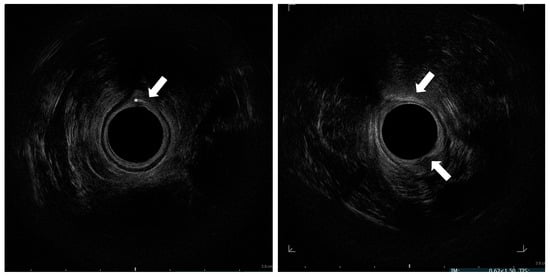

Figure 2.

Endosonographic axial sections of the middle anal canal. Asterisk: needle in the internal anal sphincter; Arrow: injected fat tissue h 6 and 12.